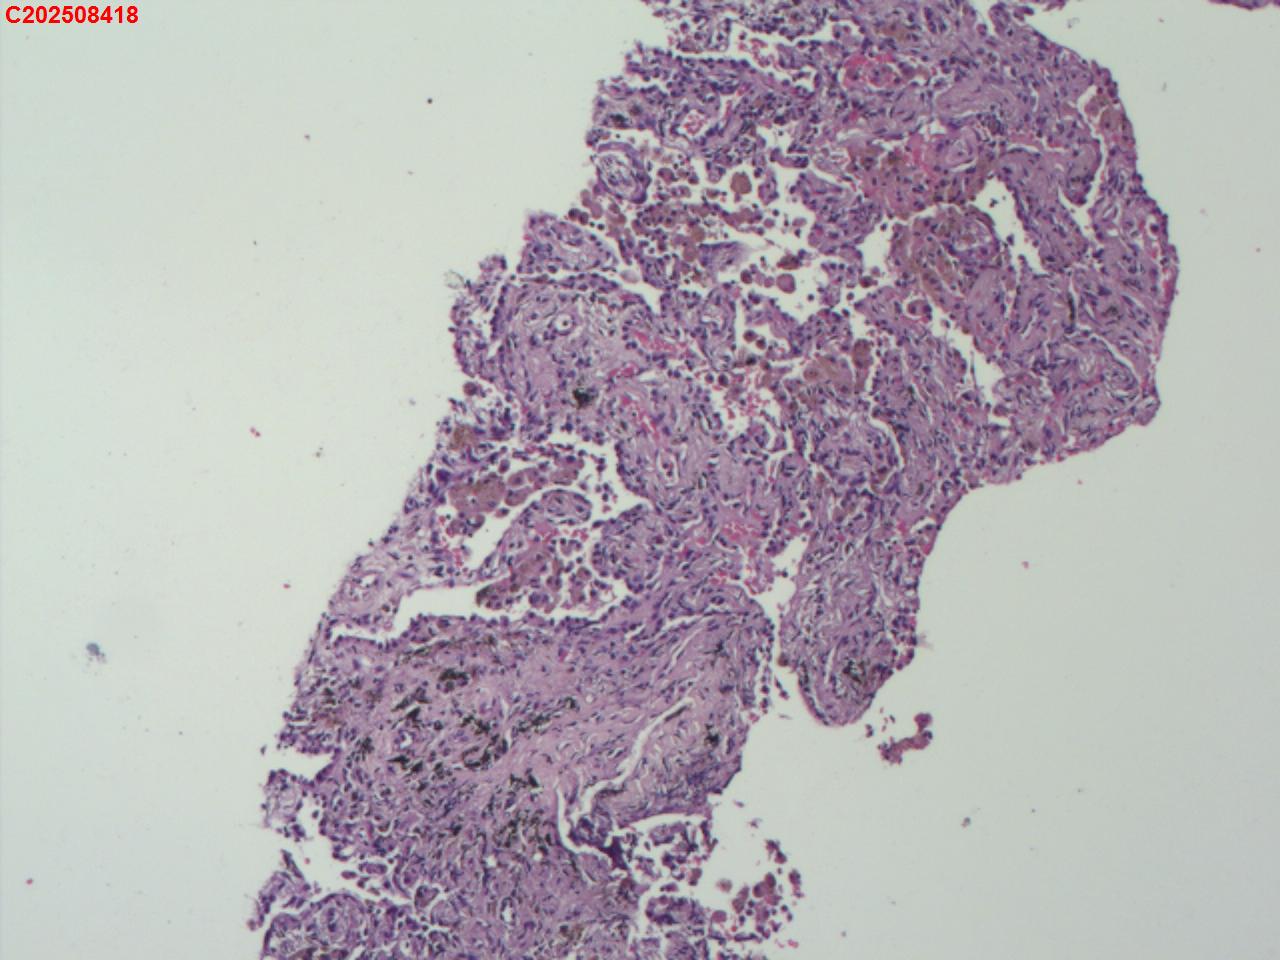

肺穿活检

性别

男

年龄

55岁

临床诊断

肺部感染?结核?占位?

一般病史

胸部(平扫+增强扫描):右肺上叶不均匀强化区,考虑1.结核伴纤维组织增生、炎性细胞浸润,2.占位性病变,请结合临床建议结合病理学检查。右肺上叶多形性病变,结核不除外。考虑为双肺细支气管炎;右肺下叶局限性间质性改变可能,坠积性肺炎不除外。左肺下叶条索影。右侧胸膜局部肥厚、粘连。

标本名称

右肺上叶 穿刺组织

大体所见

肺穿活检5条

图1

首先考虑机化性肺炎。